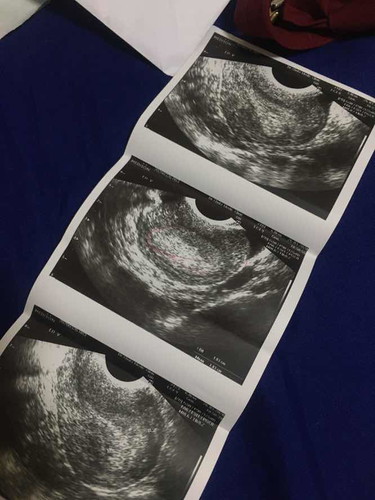

พอดีว่าตอนนี้หนูสับสนมากว่าสรุปท้องหรือไม่ท้อง เมื่อวานไปโรงพยาบาลมา ตรวจกับเจาะเลือดหมอบอกว่าท้อง กำลังท้องอ่อน วันนี้มาคลีนิคหมอบอกว่าเป็นของเก่าที่ตกค้างต้องขูดออก งงมากเลยค่ะ สรุปยังไงกันแน่ แต่ตอนนี้ก็เชื่อที่ตรวจที่โรงบาลนะคะแต่แค่ไม่มั่นใจ

คือมองไม่เห็นถุงตั้งครรภ์แม่ช่วยวงให้ดูหน่อยได้มั้ยคะว่าถุงตั้งครรภ์อยู่ตรงไหน

ตรงไหนถุงตั้งครรภ์คะ เหมือนไม่มีถุงตั้งครรภ์เลยค่ะ

ถุงตั้งครรภ์กับตัวอ่อนมันไม่เหมือนกันเข้าใจป่ะ ถึงไม่มีตัวอ่อนก็ต้องมีถุงตั้งครรภ์แต่ในใบซาวด์ไม่มีถุงตั้งครรภ์อะไรเลย